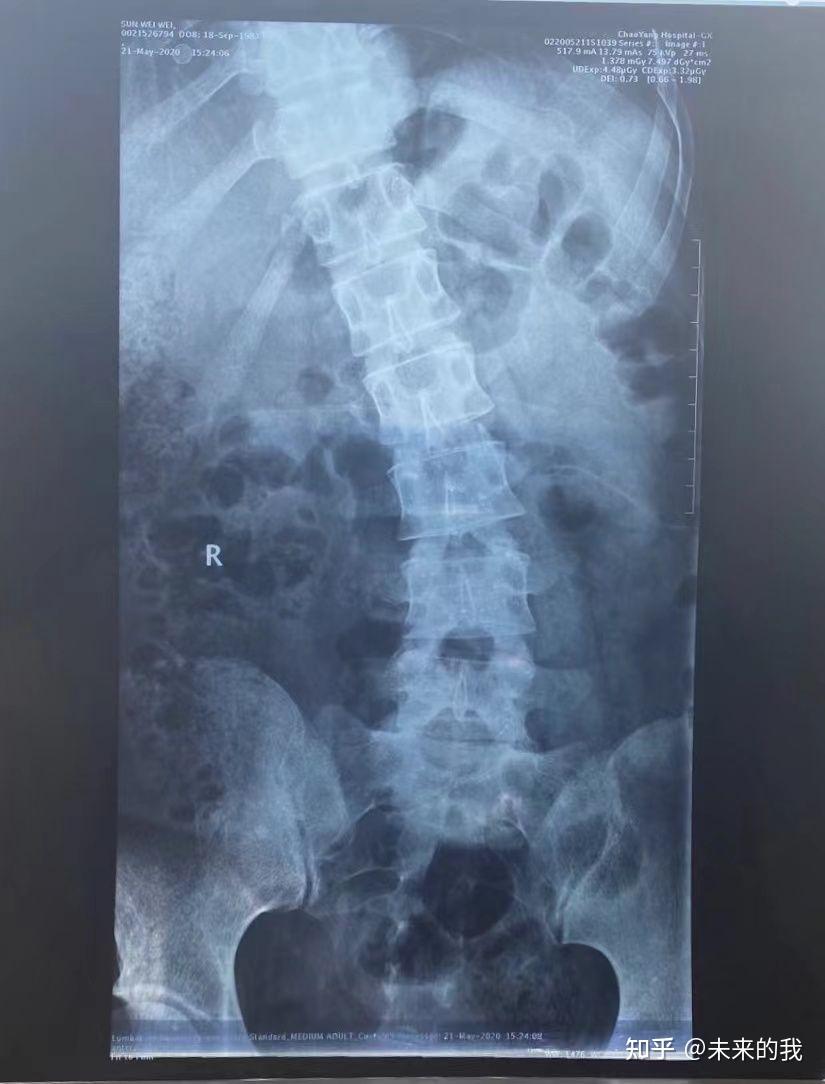

我是腰四五,腰五骶一突出,但那时,我的关注点并不在这里,唯一的目的结果就是怎样能治好我的病就行,不再让我这么难受就行。无论用什么方法……!!!

过了有10天左右,我想了想,还是决定去地区级的三甲医院,再去看看,再这里要说一下,这个地区级的三甲医院,也是在我们市,属于保定市唯一的住外医疗机构,和我们市医院也就是相距几里路。不同的就是一个是地市级的三甲医院,一个是县市级的医院,。到了这个三甲医院后,挂的也是一个专家号,让我特别不理解的是,仅仅是相隔了10天,这个专家竟然让我再去照一个核磁,解释就是只对本医院的检查报告负责,说白了就是别家医院的不认可,要知道,这两家医院的硬件水平在整个保定市都属于一流的,只不过我们市级别不是三甲而已,但市医院多年来经常都是请一些北京的大医院大夫来坐诊,医疗水平也是可以的,但都到了医院了!!我也是没办法,只能重新去照片了,

当时照核磁800,那可是十几年前啊,感觉自己就像案板上的肉任人宰割……。结果出来后,和10天前的也没什么区别,就是四五,和骶一,尤其是骶一突出很多,这个专家又给我做了一番检查,直腿抬高试验等,还用小锤敲一敲膝盖,看反射能力等,全部检查完都下午三点了,结论就是让我做手术,说骶一突出比较多,,我说回去考虑考虑,回家后总觉得不靠谱,也就没有再去这家医院了,